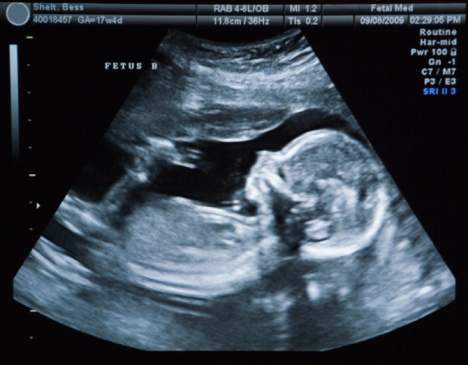

سونوگرافی

سونوگرافی یک راه غیرمخرب برای تعیین جنسیت جنین است؛ استفاده از سونوگرافی برای تعیین جنسیت جنین فقط از هفته های ۱۸ تا ۲۰ به بعد ممکن است.

تکنسین اولتراسوند ممکن است در هنگام اسکن نتواند جنسیت جنین را تشخیص دهد زیرا ممکن است جنین در موقعیت ایده آل قرار نداشته باشد یا بارداری به اندازه کافی پیشرفت نکرده باشد.